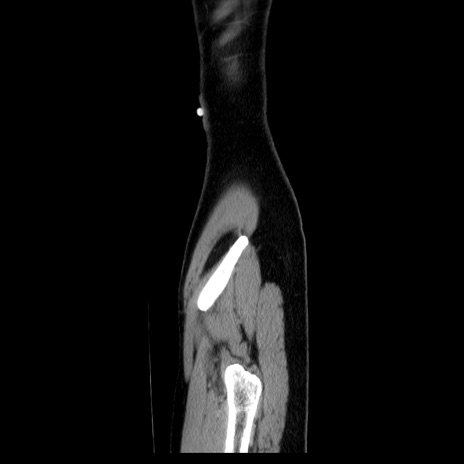

症例39(矢状断像)

【症例】40歳代女性

【主訴】上下腹部痛

【現病歴】2日目から下腹部痛あり。夜間は痛みで眠れなかった。昨日より上腹部痛と下痢が出現。臥位で痛みは軽快したため、休んでいた。本日になって臥位でも立位でも痛みが強くなってきたため救急要請。

【既往歴】子宮内膜症

【身体所見】部:平坦・軟、左上下腹部に圧痛あり、反跳痛あり。

【データ】WBC 21800、CRP 26.78

CT